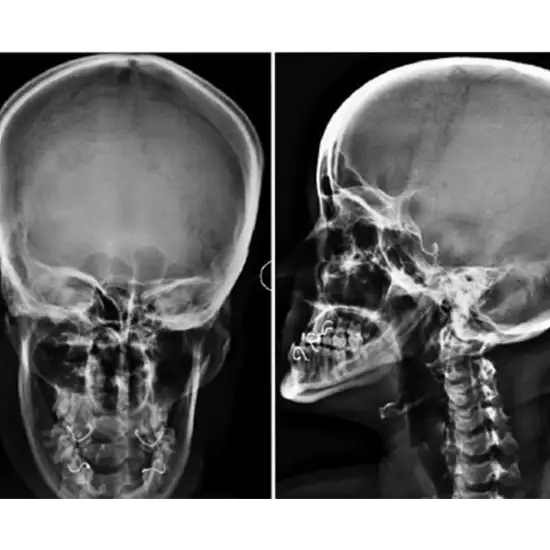

The skull anteroposterior (AP) view is a specific skull radiograph. This view offers an overview of the whole skull rather than striving to highlight any one region.